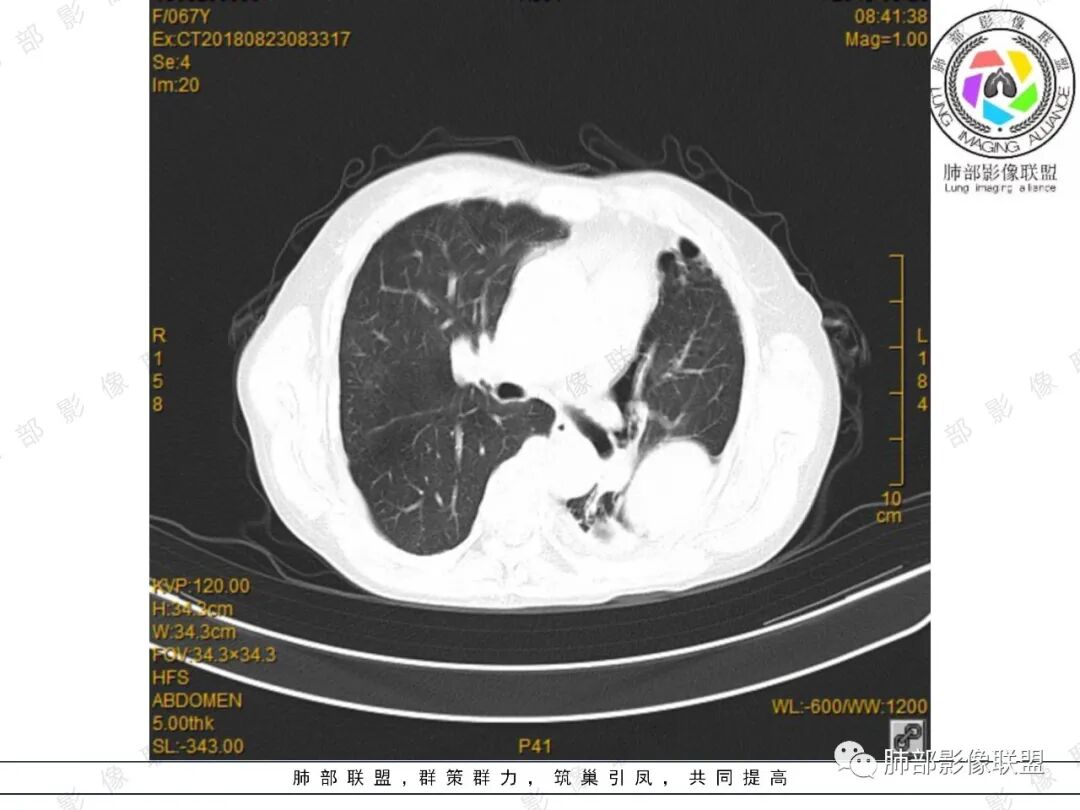

采莲:中年女性,有便血病史,左肺上叶椭圆形肿块,边缘光滑,长轴与胸膜平行,与胸膜宽基底相连,内部密度较均匀,有低密度区,密度较高,强化不明显,脊柱旁胸膜增厚,有便血病史,不知道是不是慢性,考虑来源胸膜,髓外造血?脾脏不会看。其他神经源性肿瘤?

小强:脾大,延迟强化均匀,无明显占位,左胸膜下孤性增厚,局限性膨大,强化不均匀,先考虑EMH,不太支持的是临近骨质没有膨大。

水晶石头:患者老年年女性,便血两天就诊,查NSE稍升高。胸部CT:左肺上叶类圆形肿块,边缘光滑,边界清楚,长轴与胸膜平行,与胸膜宽基底相连,内部密度较均匀,有低密度区,强化轻中度强化。综合考虑来源胸膜来源,胸膜孤立性纤维瘤可能大。鉴别其神经源性肿瘤。

月亮圆了!:左肺上叶胸膜下肿块,宽基底与胸膜相连,边缘清晰,局部肺组织受压,支气管显示不佳,平扫密度不均匀,增强后,可见轻度不均匀强化,纵隔光滑,无分叶,无毛刺,周围组织无牵拉,收缩,内部有不均匀低密度,脾脏明显肿大,脾内多发类圆形低密度影,增强后,轻度强化,有便血,考虑可能:1:淋巴瘤2:脾梗死。